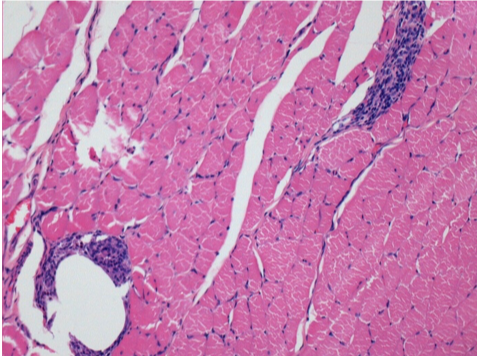

Histology

On Wistar rats

-hematoxilin-eosin

L:Pretibial-No treatment